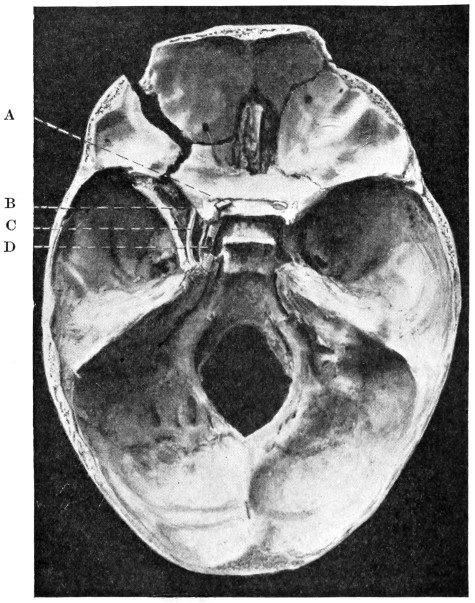

29 A and B. The base of the skull and the base as seen on transillumination 70, 71

30. Plan of the base of the skull 77

50 A and B. The inner aspect of the skull and the same seen on transillumination 137